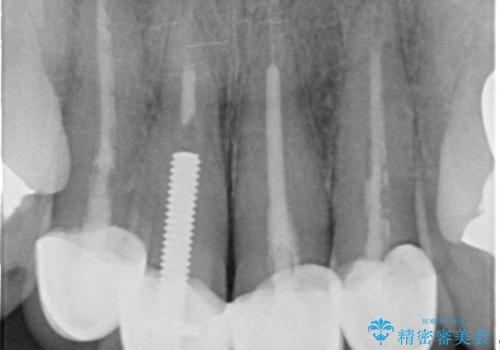

以前に治療した前歯クラウンは月日が経過することで劣化・歯肉の位置変化を引き起こし審美障害を引き起こしています。

劣化したクラウンを除去し、再発した虫歯を徹底的に除去したのち根管治療・ファイバーコア築盛を行いジルコニアクラウン製作へと移ります。

- 52万円(仮歯・ファイバーコア・ジルコニアクラウン×4)費用は治療当時の料金となります